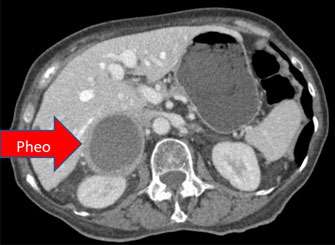

In contrast, approximately 1/3 of pheochromocytoma cases are now known to be genetic, which means that they have a hereditary or familial association. The most common associated genetic conditions are Multiple Endocrine Neoplasia (MEN) type 2 and von Hippel-Lindau Syndrome, followed by Neurofibromatosis type 1 and Familial Paraganglioma Syndrome (which is caused by mutations in the succinate dehydrogenase gene). We recommend genetic counseling for all patients with pheochromocytoma or paraganglioma, as this can provide important information for the patient’s prognosis and earlier screening for family members.

The cause of MEN II is genetic -- a mutation in a gene called RET. Multiple tumors may appear in the same person, but not necessarily at the same time. The adrenal tumor is a pheochromocytoma and the thyroid tumor is a medullary carcinoma of the thyroid. The disorder may occur at any age, and affects men and women equally. The main risk factor is a family history of MEN II.

This syndrome is caused by a mutation in the VHL gene that helps prevent the growth of tumors. Approximately 10-34% of patients with VHL syndrome may develop pheochromocytomas or paragangliomas, in addition to hemoangioblastomas, retinal angiomas, renal cell cancers, and neuroendocrine tumors of the pancreas.